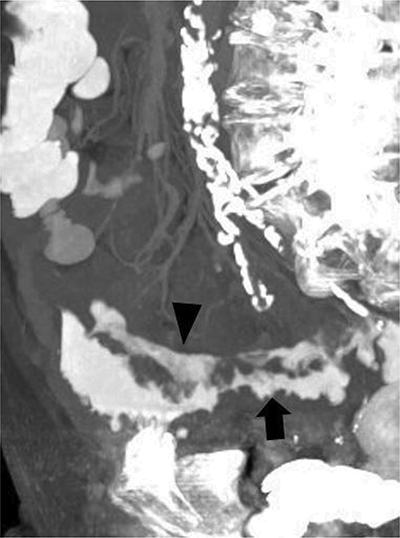

Figure 1

Maximum intensity projection imaging of the abdominal CT: two contrast trajectories are distinguishable, the intramural longitudinal fistula (arrowhead) and the normal intraluminal contrast of the sigmoid (arrow).